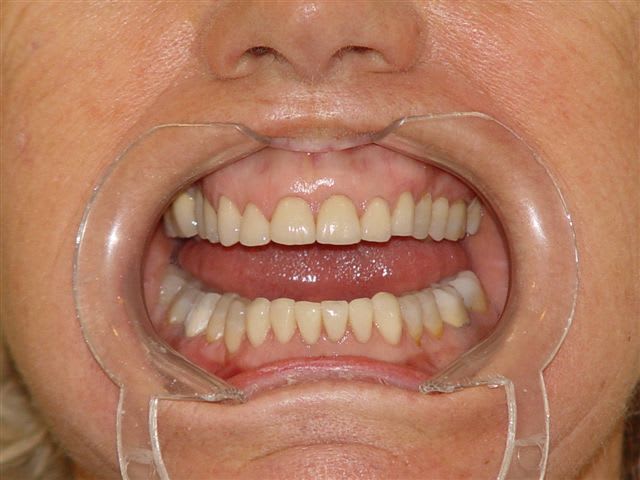

pour info et sans chirurgie, juste avec un machouilleur et le cerec

Perte de dvo laf6bw - Eugenol

Dvo à restaurer qjd6xd - Eugenol

Ainsi ntouaf - Eugenol

Cerec et e max xh3pat - Eugenol

Quand on voit l'usure des dents et la dvo actuelle, on peut tenter de réhausser les dents en désocclusion par des onlays comme je l'ai montré ci dessus, d'autant plus qu'à 78 ans le grand père de fluornet ne doit pas mourrir d'envie de repasser sur le billard avec un pronostic plus qu'alléatoire à mon humble avis, mais je pense que tout le monde a compris que je ne suis pas la diva du bistouri ce que je revendique haut et fort, les résultats de la dentosophie étant souvent bien plus satisfaisants que ceux des interventions chirurgicales maxillofaciales lourdes.